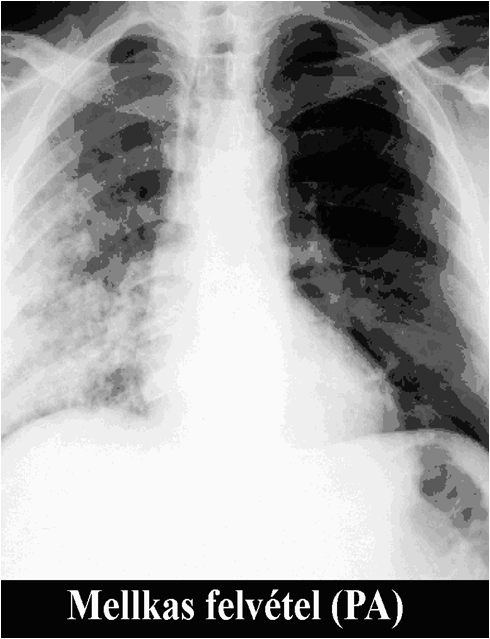

The brightness of the picture can also be altered, making too dark or too light parts of the picture assessable. The windowing allows changing of the brightness and contrast at the same time. If we change them accordingly tissues with different absorption can be highlighted. For example, low brightness and low contrast settings allows good visualization of the bone structures, but other tissues appear moderately pale. High brightness and contrast settings results in a good visualization of the lung tissue while other tissues appear bright and pale.

Figure 3.: The same CT image with soft tissue window (a) and lung window (b)